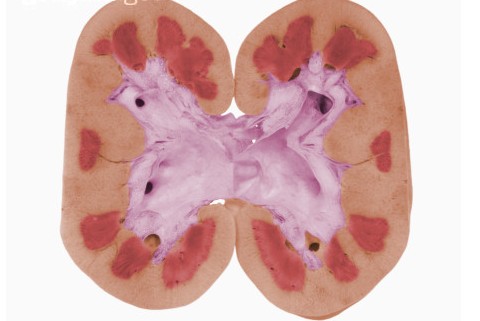

肾盂肾炎属于一种炎症,分为急性肾盂肾炎和慢性肾盂肾炎。一般由外来病菌入侵,随着血液循环后进入肾单位中;但它们会破坏肾小球、肾小囊和肾小管本身的功能,轻微地影响着人体的原尿形成和最终尿液的排出。

慢性肾盂肾炎多发生于尿路解剖或功能异常的基础之上,除了细菌性尿感外,还有肾盂肾盏瘢痕形成,肾脏外形不光滑或两肾大小不等,起病较为隐匿,容易反复发作,可导致慢性肾功能不全,严重者会走向肾衰竭。